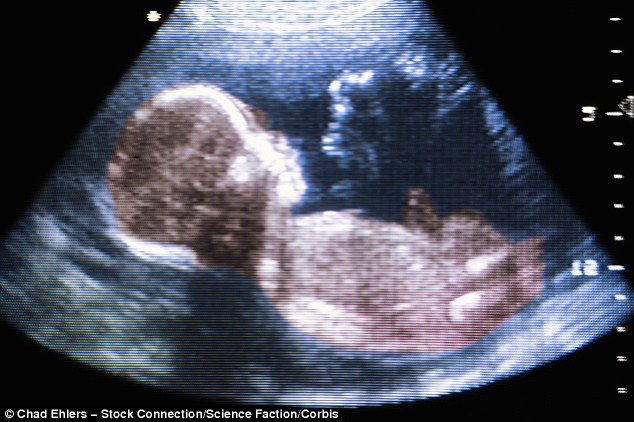

Many researchers have theorized that a pregnant woman’s exposure to chemical pollutants, particularly metals and pesticides, could be altering a developing baby’s brain structure, triggering autism.

In addition, fetuses and infants might be exposed to a fairly new infectious microbe, such as a virus or bacterium, that could be altering the immune system or brain structure. In the 1970s, autism rates increased due to the rubella virus.